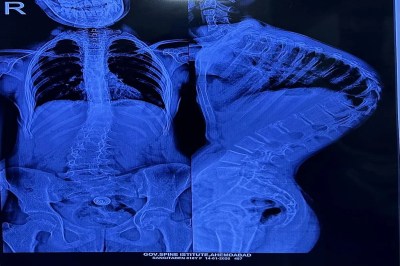

सर्जरी के बाद और पहले।

Ahmedabad. सिविल मेडिसिटी के गवर्नमेंट स्पाइन इंस्टीट्यूट ने एक बार फिर चिकित्सा नवाचार और मानवीय सेवा का अद्भुत उदाहरण पेश किया है। यहां आयोजित दूसरे इंडो-अमेरिकन स्पाइन सर्जरी कैंप में सात बच्चों की जटिल काइफोस्कोलियोसिस सर्जरी सफलतापूर्वक की गई। इन बच्चों की रीढ़ की हड्डी सांप की तरह टेढ़ी-मेढ़ी हो चुकी थी, जिससे उनका जीवन […]

डॉ. मित्तल के अनुसार यह अत्यंत जोखिमपूर्ण ऑपरेशन होता है। 4 से 5 घंटे तक चलने वाली इस प्रक्रिया में रीढ़ की हड्डी को सीधा करते समय नसों और रक्तवाहिनियों के बीच बेहद सावधानी से काम करना पड़ता है। थोड़ी चूक भी मरीज को जीवनभर का लकवाग्रस्त कर सकती है। इस जोखिम को कम करने के लिए अमेरिकी न्यूरो-मॉनिटरिंग टीम और एनेस्थीसिया विशेषज्ञों ने अहम भूमिका निभाई। सर्जरी के बाद बच्चों के लिए पोस्ट-ऑपरेटिव रिहैबिलिटेशन पर भी खास ध्यान दिया जा रहा है। इस सफल प्रयोग ने साबित किया है कि उच्च तकनीक और विशेषज्ञ हाथ मिलकर आम लोगों के जीवन में बड़ा बदलाव ला सकते हैं।